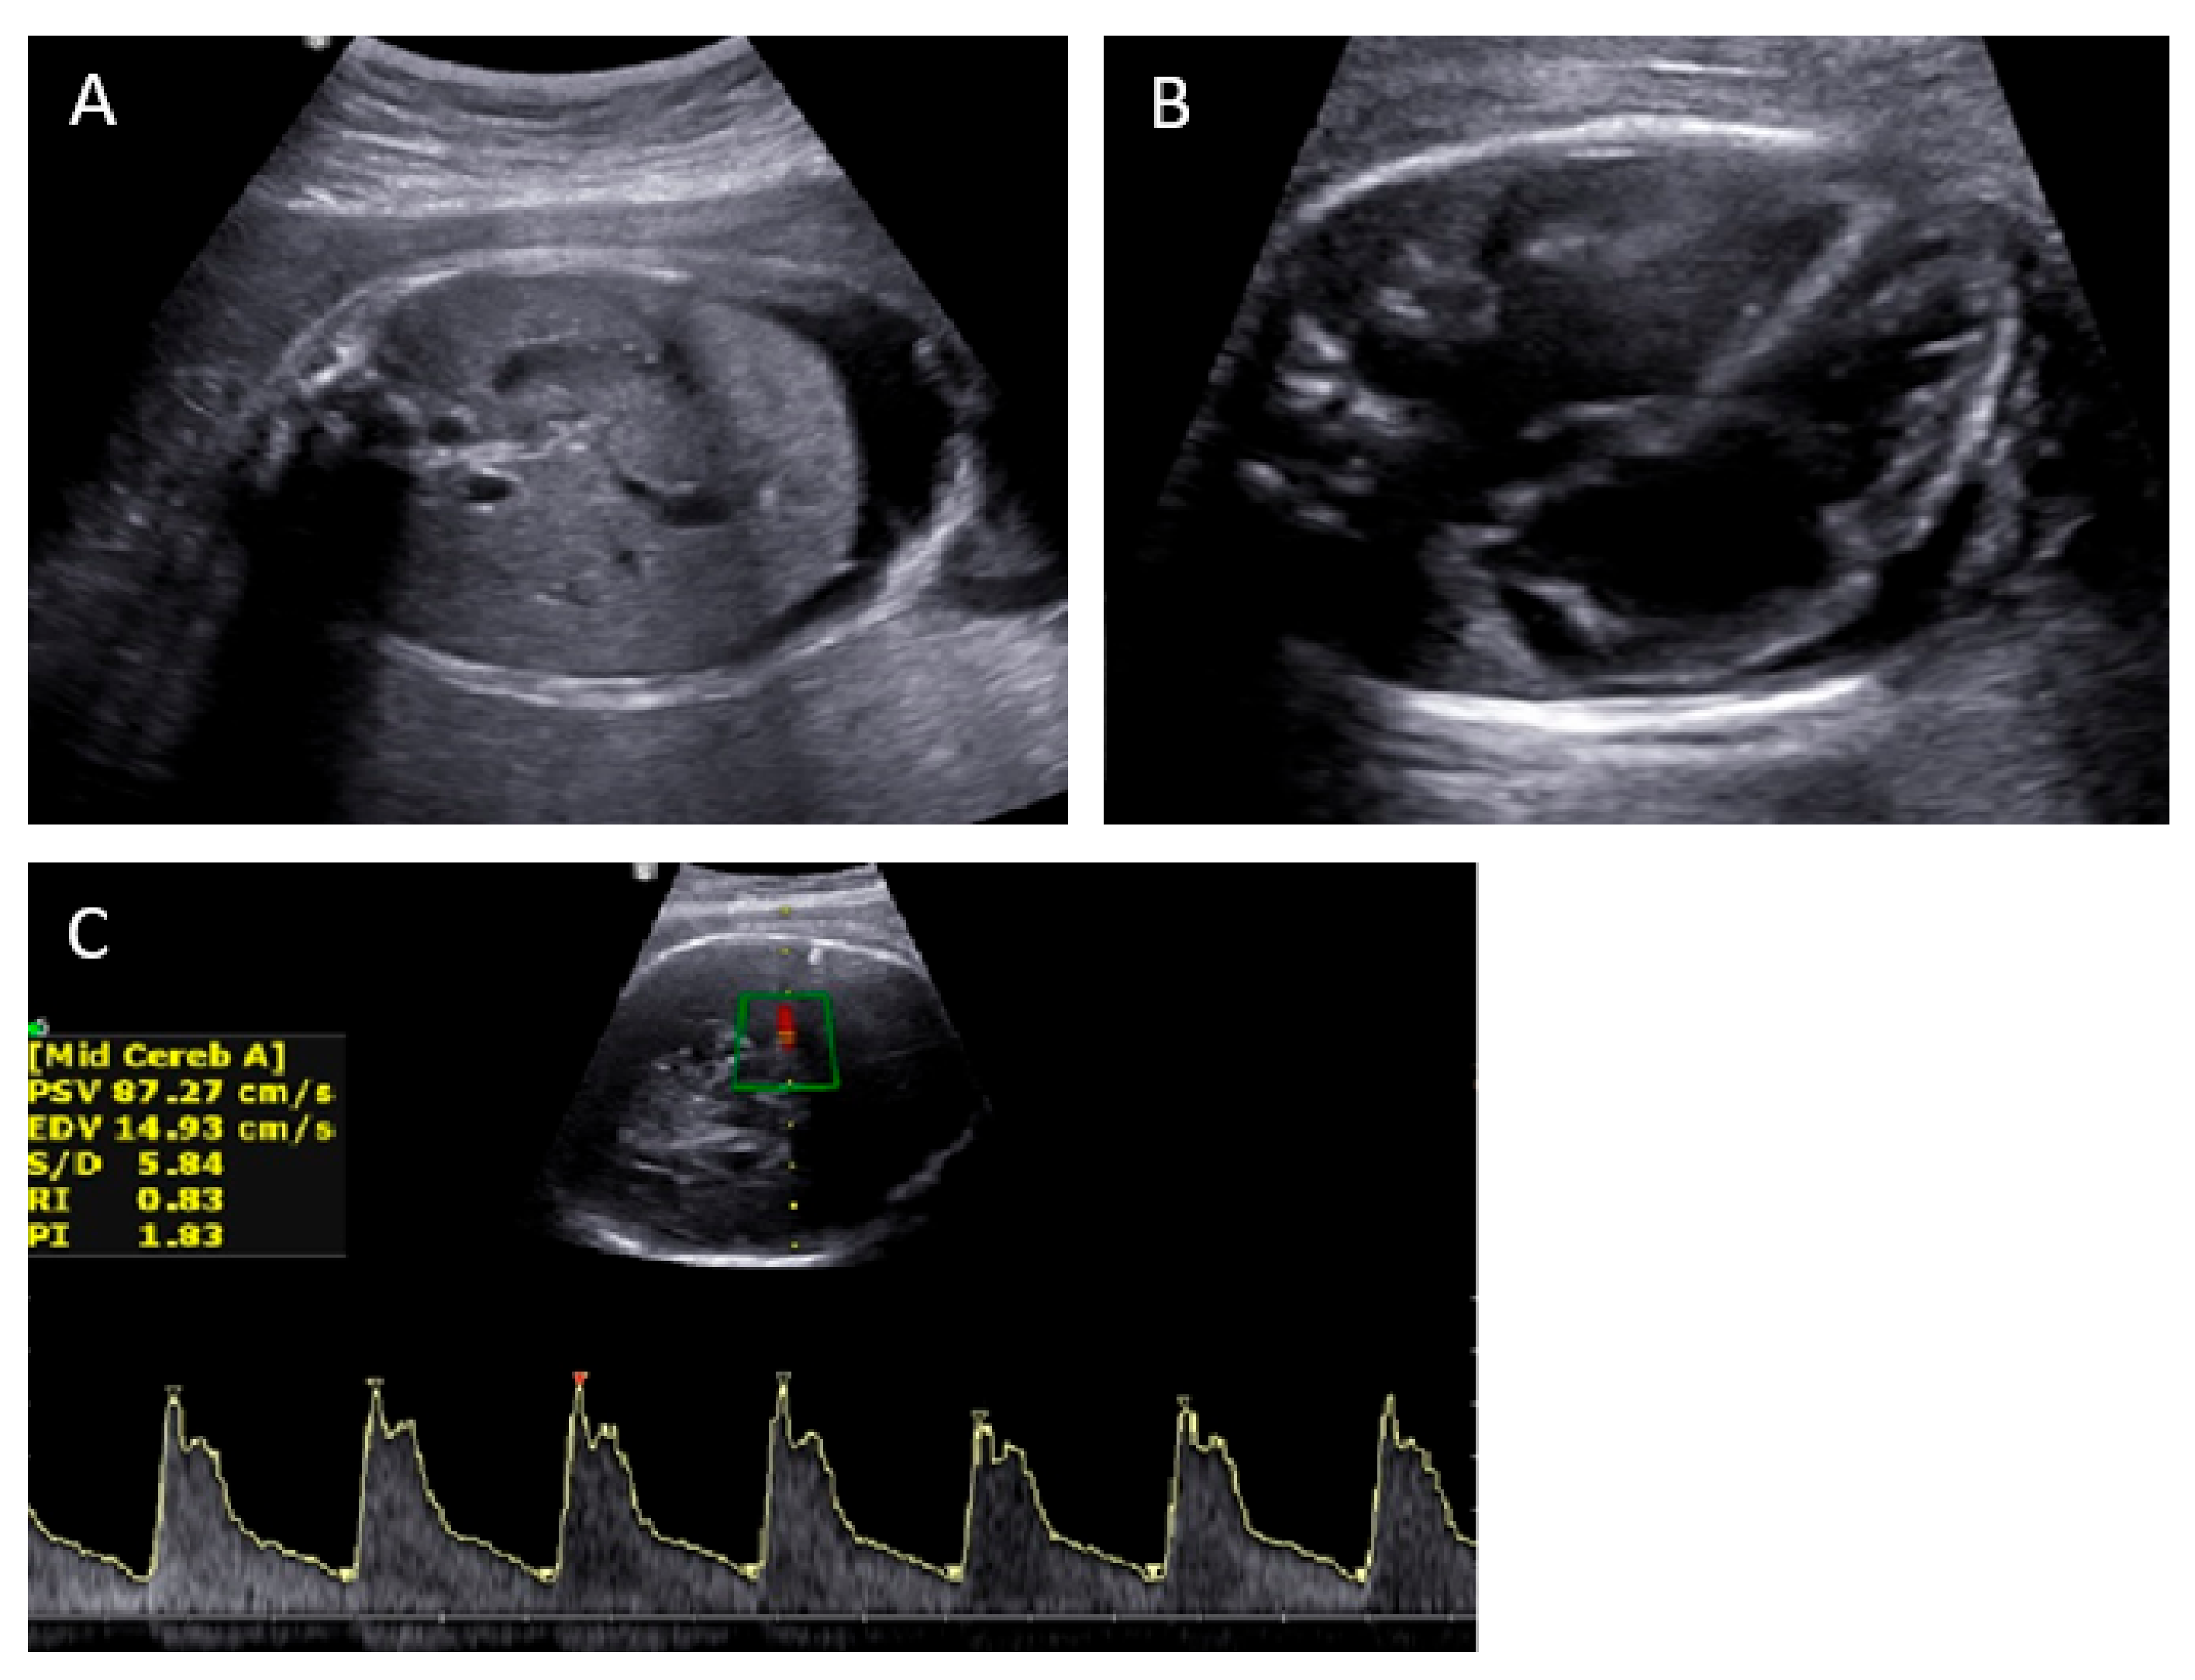

2. Case Presentation